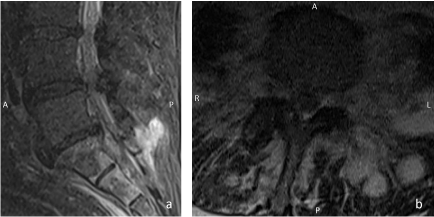

Besides, edema zones could be detected in the sacrum (Figure 1). A native computed tomography (CT) scan of the abdomen was obtained for further clarification and search of infection focus. Here, a slightly inhomogeneous fluid collection in the left retroperitoneum was detected. It showed a close positional relationship to the ovary and the sacrum. Adjacent to this, extensive intraosseous punctate gas accumulations were seen in the first sacral vertebra, mainly on the right side (Figure 2). The spinal canal and adjacent soft tissues showed no gas accumulation, and no cortical destruction could be detected. Also, an unclear foreign body was detected in the cervix (not shown).

Figure 1: Sagittal (a) STIR-image (short-tau-inversion-recovery) shows edema in the sacrum as well as fluid collections in the Back musculature. Transversal T2-image (b) shows left-sided fluid collections in the back musculature and psoas muscle.